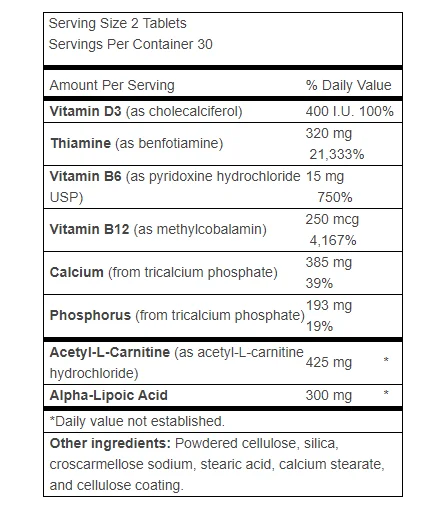

That is why we made a product named Advanced Nerve Support. It gives the same amount of benfotiamine used in the tests. It also has four more helpful things added to it…

You get the same helpful amount of methylcobalamin in Advanced Nerve Support.

With this special deal, you may get Advanced Nerve Support for just $41.50 per bottle. That gives you a saving of up to $77.25 each month. You do not need to buy every nutrient one by one. Everything comes in one simple formula. No mixing. No guessing. All is ready to use. Also, the methylcobalamin inside helps the other parts work better. That means better support for your nerves, without any extra steps.

You get the full dose of Alpha Lipoic Acid in Advanced Nerve Support. But that’s not all—you also receive…

You receive all five of these strong helpers in just one simple bottle of Advanced Nerve Support.